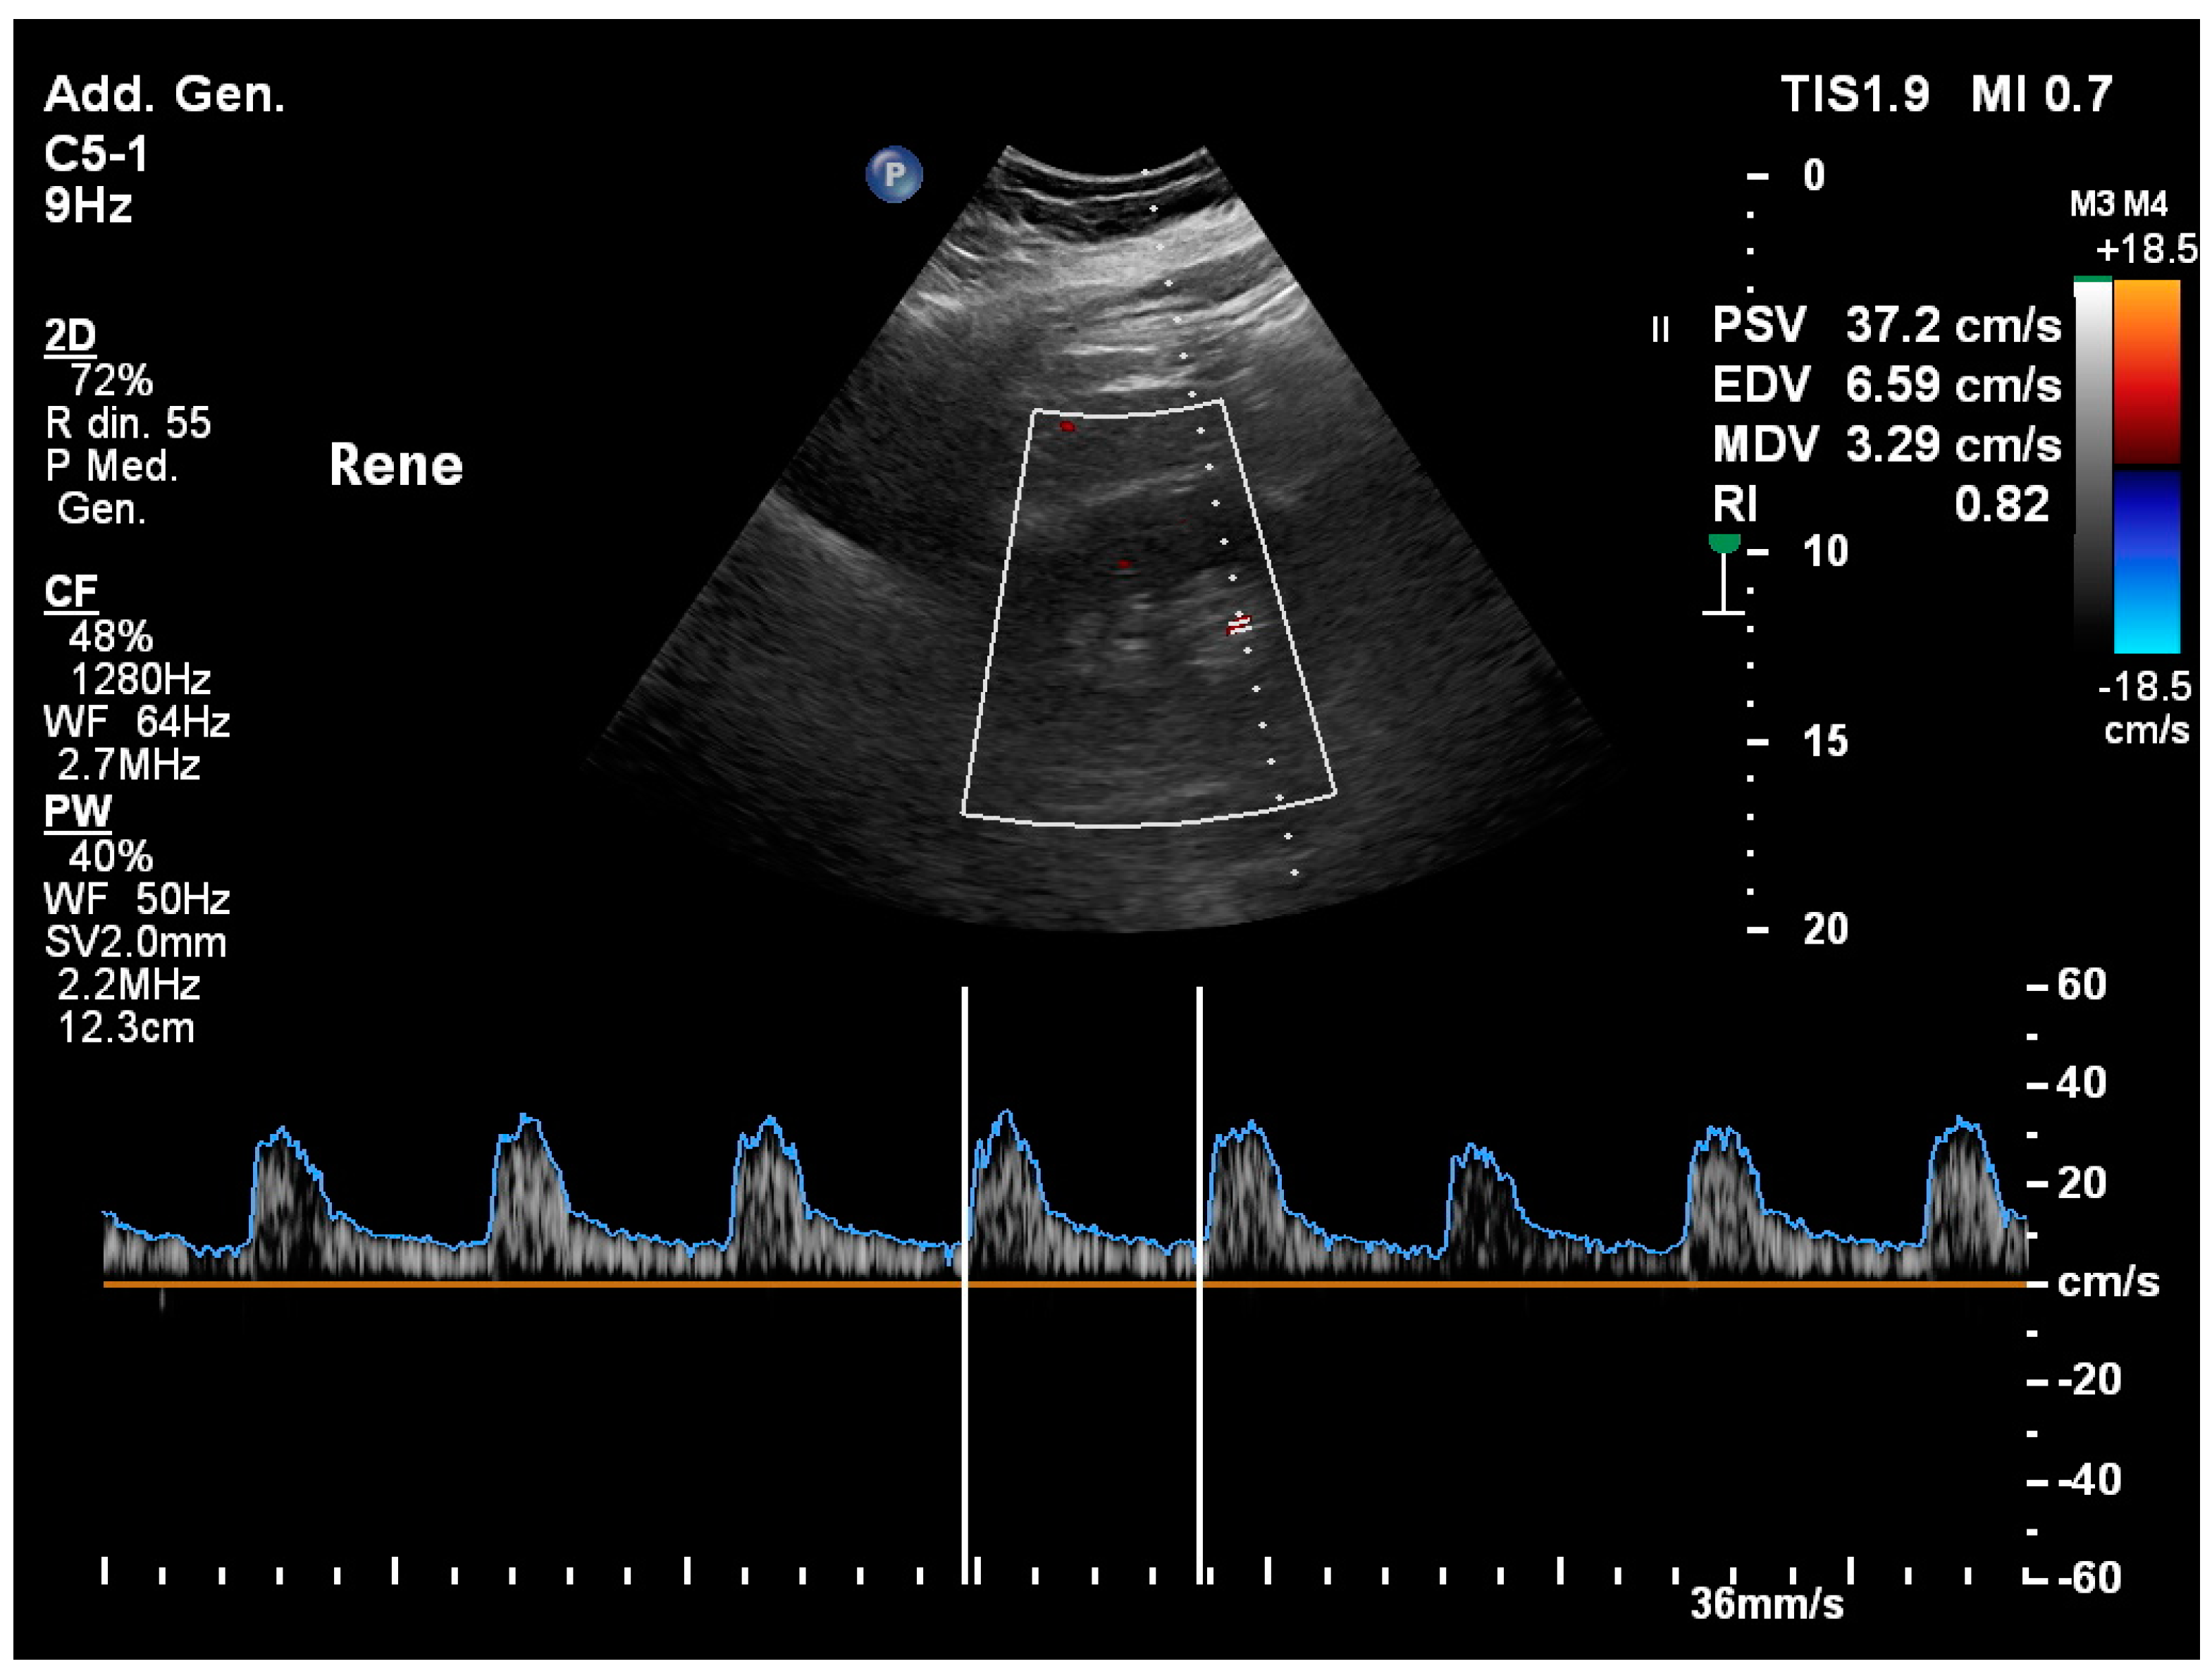

3.13. Renal Resistivity Index

3.2. Acute Kidney Injury